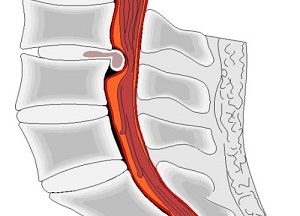

Kidudorodás - porckorong kiemelkedés túl a gerinc, annulus miközben annak integritását. Dorsal (dorzális, posterior) kiemelkedés egy kiemelkedés felé gerinccsatorna, amely provokálja épségének megsértése az ideg gyökerek, megjelenése kellemetlen tüneteket drámaian.

Háti kiemelkedés orvosi gyakorlatban nagyon gyakran egy kedvenc helye a lokalizáció: nyaki, ágyéki gerinc (ezeken a területeken a napi ellenáll a nehéz terhek, amelyek érzékenyek a különböző betegségek). Patológia a legveszélyesebb az összes kiemelkedések, mint a kiemelkedés felé irányul gerincvelői struktúrák, a valószínűsége, idegek károsodása, a kialakulása egy komplett sérv, ami a beteg fogyatékosság végül.

Egy sor negatív tényezők provokál egy bizonyos változás a szerkezet a porckorong rostos gyűrű rostos szövetek betegségei. A rostos gyűrű a héj nem törött, de megfigyelhető kiemelkedés túl a gerinc.